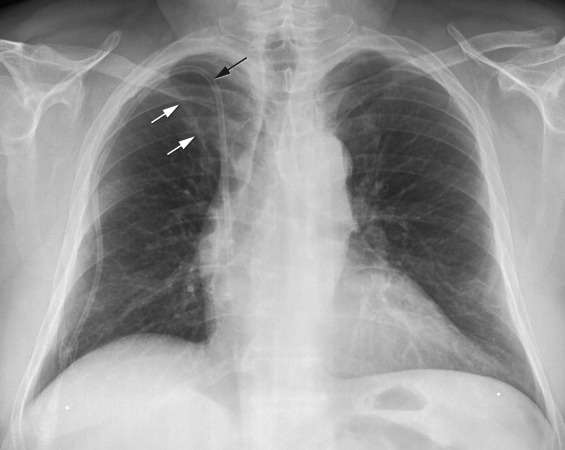

Right-sided pneumothorax

Pneumothorax

Feature Description

Visceral pleural line Thin sharp white line marking the lung edge, separated from chest wall.

Absence of lung markings No pulmonary vascular markings peripheral to the visceral pleural line.

Deep sulcus sign In supine films, abnormally deep and lucent costophrenic angle suggesting an anterior pneumothorax.